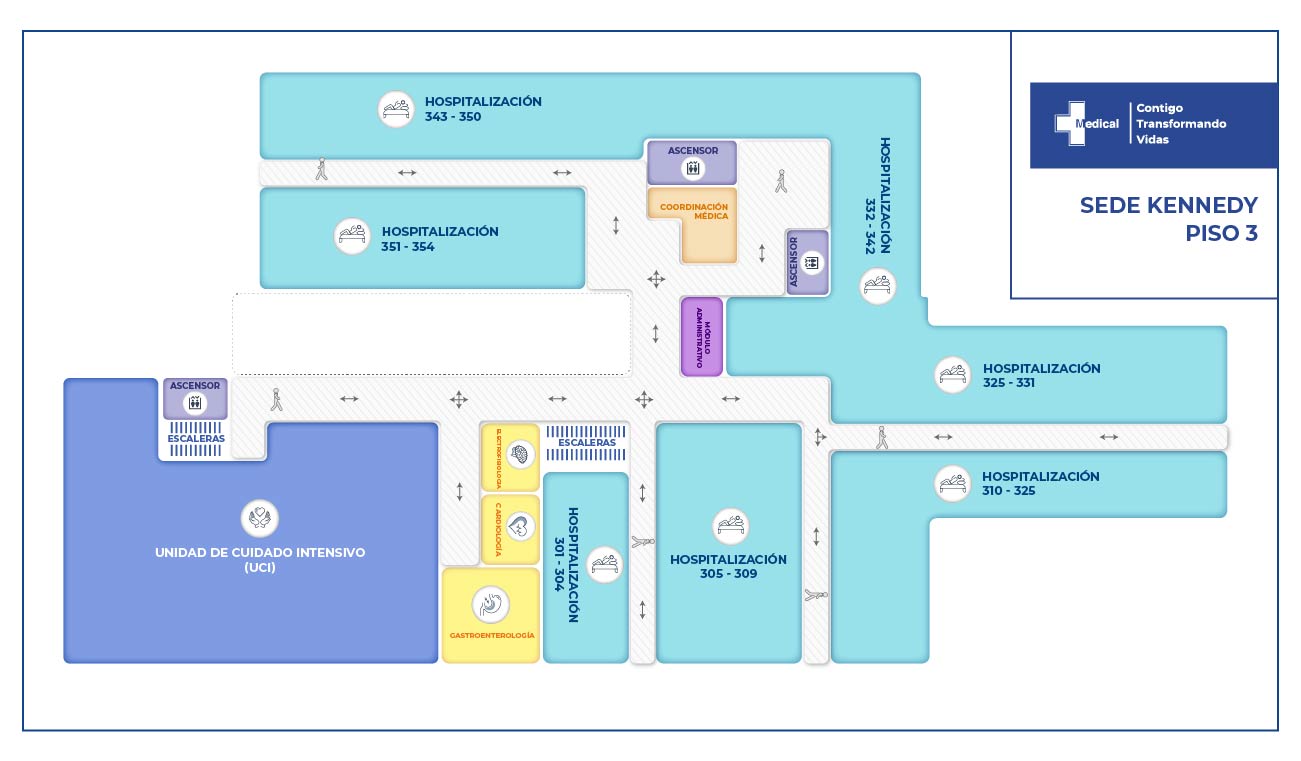

La condición de ingreso es realmente poco alentadora, sin embargo la oportunidad de los servicios, la eficiencia y eficacia que caracteriza a la clínica Medical SAS, ofrece al paciente y su familia todo un equipo interdisciplinario para la atención adecuada y secuencial para este tipo de traumas. Precedida por especialistas en cirugía general, neurocirugía, psicología, psiquiatría, servicios de apoyo terapéutico y radiológico, salas de cirugía, unidad de cuidados intensivos, rehabilitación física, clínica de heridas, entre otros.

Desde el ingreso fue claro que el paciente no recobraría la movilidad de las piernas dada a la sección medular completa, sin embargo el equipo de especialistas intervino al paciente con la finalidad de evitar deformidad mayor en la columna vertebral, disminuir el riesgo de fracturas a otro nivel vertebral, adopción de una postura más estable, disminución de dolor. Todas ellas enfocadas en brindar al joven paciente una opción de mejorar su calidad de vida.